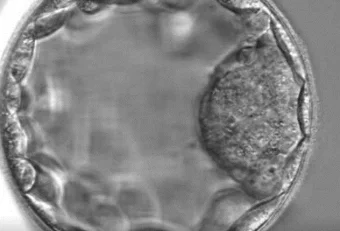

Blastozyste: ein fünf Tage alter Embryo

Die meisten Embryotransfers erfolgen bei einer Kinderwunschbehandlung am fünften Tag, wenn sich der Embryo im Stadium einer Blastozyste befindet. Doch was ist eine Blastozyste genau und warum ist dieses Stadium so wichtig?